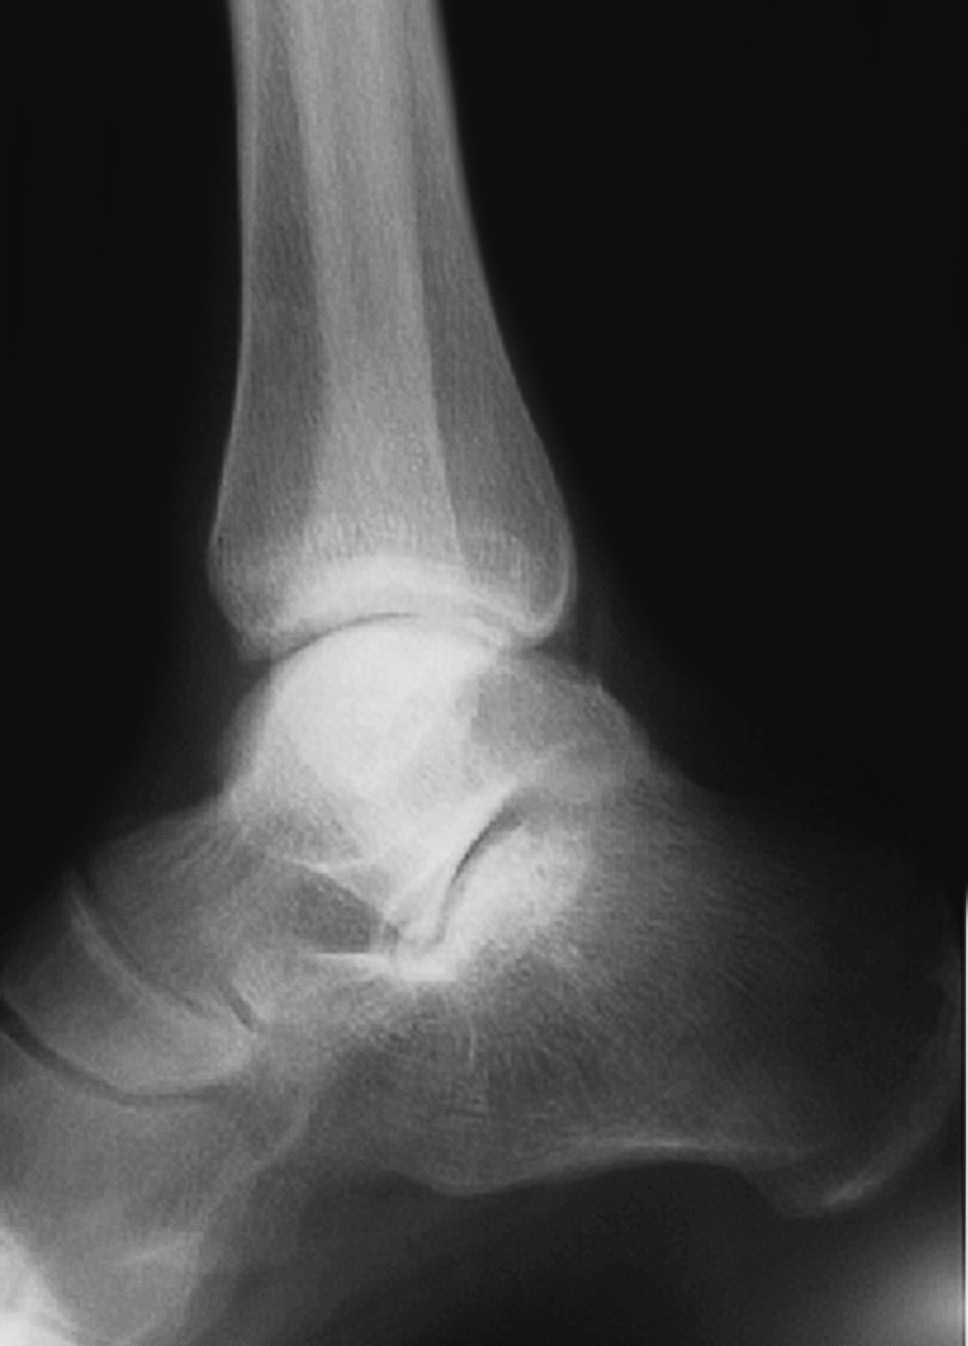

El seguimiento a la largo plazo de las fracturas del astrágalo identifica que la causa más común de los resultados pobres está asociada con la OA subastragalina, tibioastragalina y talonavicular, tanto en nuestra revisión, que alcanzó al 21% (8) de los casos (figs. 9 y 10), como en otros trabajos revisados15,17,19,22,23.

Fig. 9. --A) Fractura del cuerpo del astrágalo tipo B más rotura completa de los 3 ligamentos laterales del tobillo. B) Abordaje bilateral. Osteosíntesis. Sutura de ligamentos. Radiografía y tomografía computarizada a los 18 meses. Artrosis subastragalina y tibioastragalina.

Fig. 9. --a: Type B fracture of the astragalus with complete rupture of the 3 lateral ankle ligaments. b: Bilateral approach. Osteosynthesis. Ligament suture. Radiography and CT at 18 months. Sub-astragalar and tibio-astragalar arthrosis.

Fig.10. --Resultado a los 32 meses. 50° de BA. NAV del cuerpo y artrosis subastragalina y tibioastragalina

Fig.10. --Results at 32 months. BA 50º. Avascular necrosis of the astragalus and sub-astragalar and tibio-astragalar arthrosis.